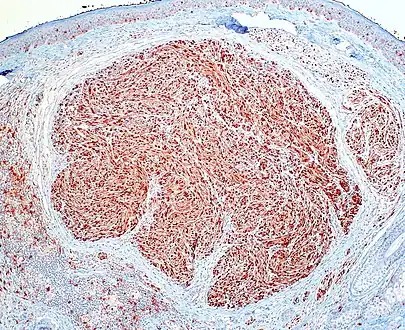

| Micrograph of a palisaded encapsulated neuroma | |

PEN is diagnosed by clinical recognition of the lesion and on subsequent histologic examination. Typically, the lesions are suspected to be schwannomas or neurofibromas clinically with PEN being an incidental finding on histology.[3]

PEN is typically diagnosed in patients between the ages of 40 and 60 years and occurs more frequently in females than males. The diagnosis of PEN may be difficult, even with confirmatory histology, due to its histological similarities with schwannomas and neurofibromas. It is imperative that the correct diagnosis is made the misdiagnosis of a neurofibroma may lead to unnecessary further investigation into associated systemic syndromes such as neurofibromatosis type 1 or multiple endocrine neoplasia syndrome.[3][4]